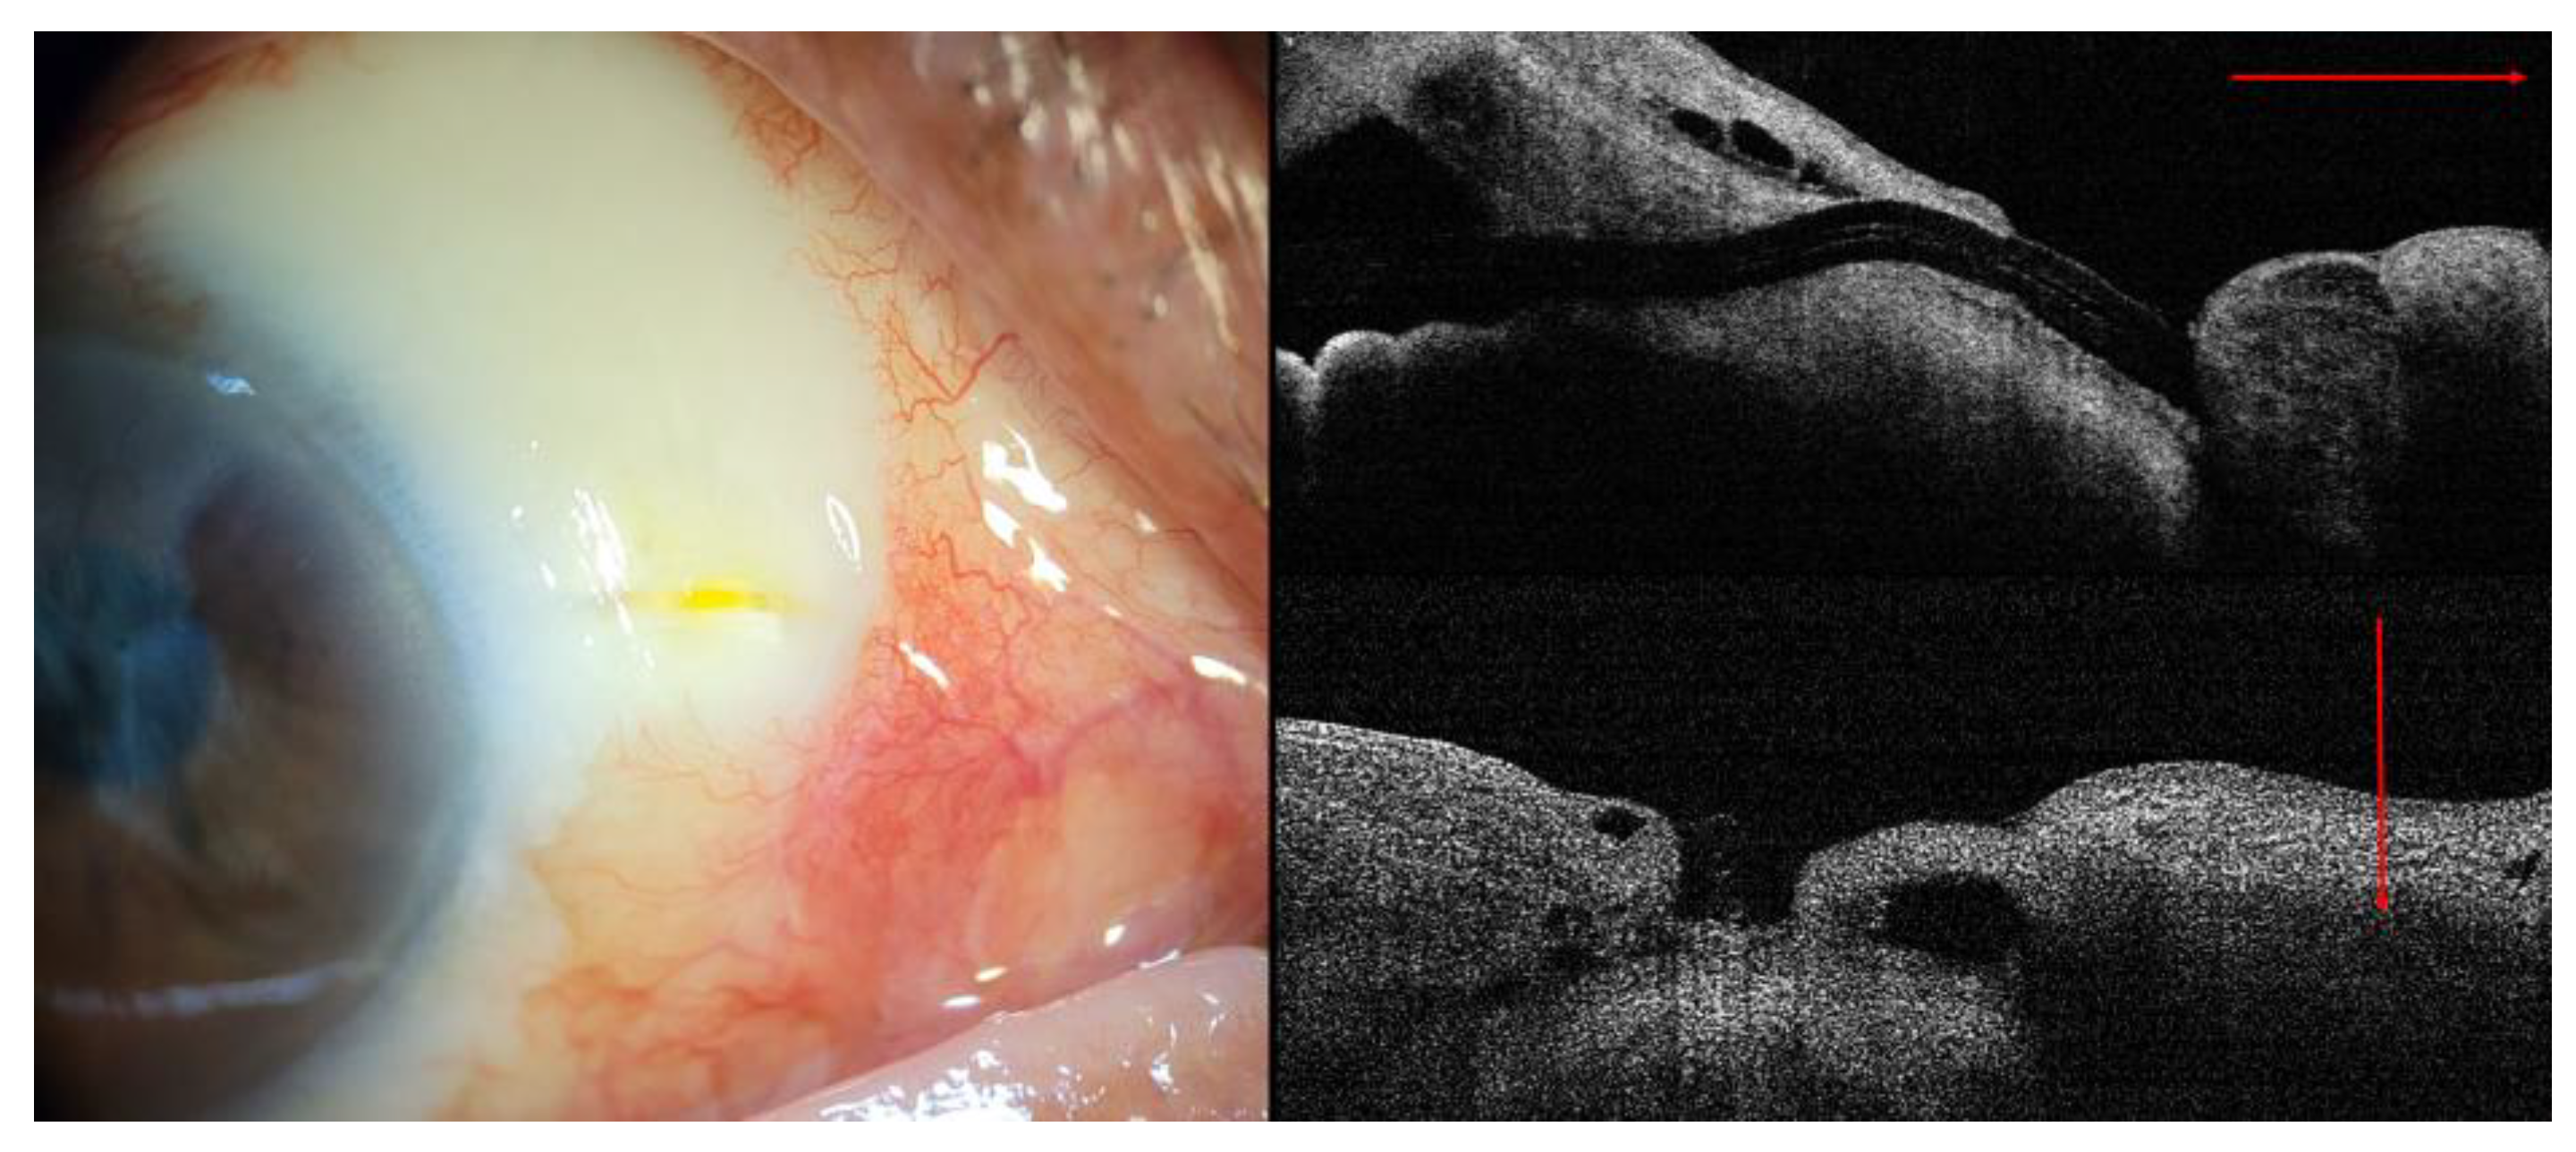

The IOP was 11 mm Hg on day 1 and 10 mm Hg on day 7. Slit-lamp examination and anterior segment optical coherence tomography (AS-OCT) revealed a well-functioning bleb (Figure 2).

Figure 2. Anterior segment photography and AS-OCT demonstrated relatively well-functioning filtering bleb at 7 days after XEN implantation. (Black line: linear scan line on AS-OCT).